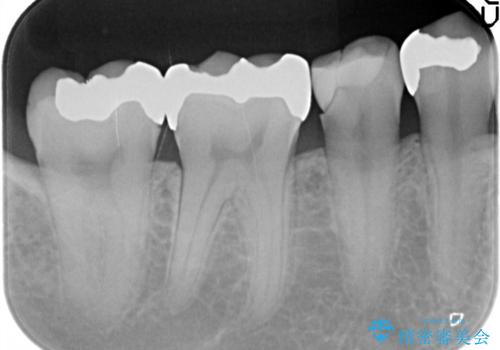

- 主訴:下の歯に入っている銀歯が笑うと目立つので白くしたい。

下顎臼歯部に入っている保険適用のメタルインレー(4箇所)を、審美性・適合性・清掃性の良いセラミックインレーにてやり替えました。